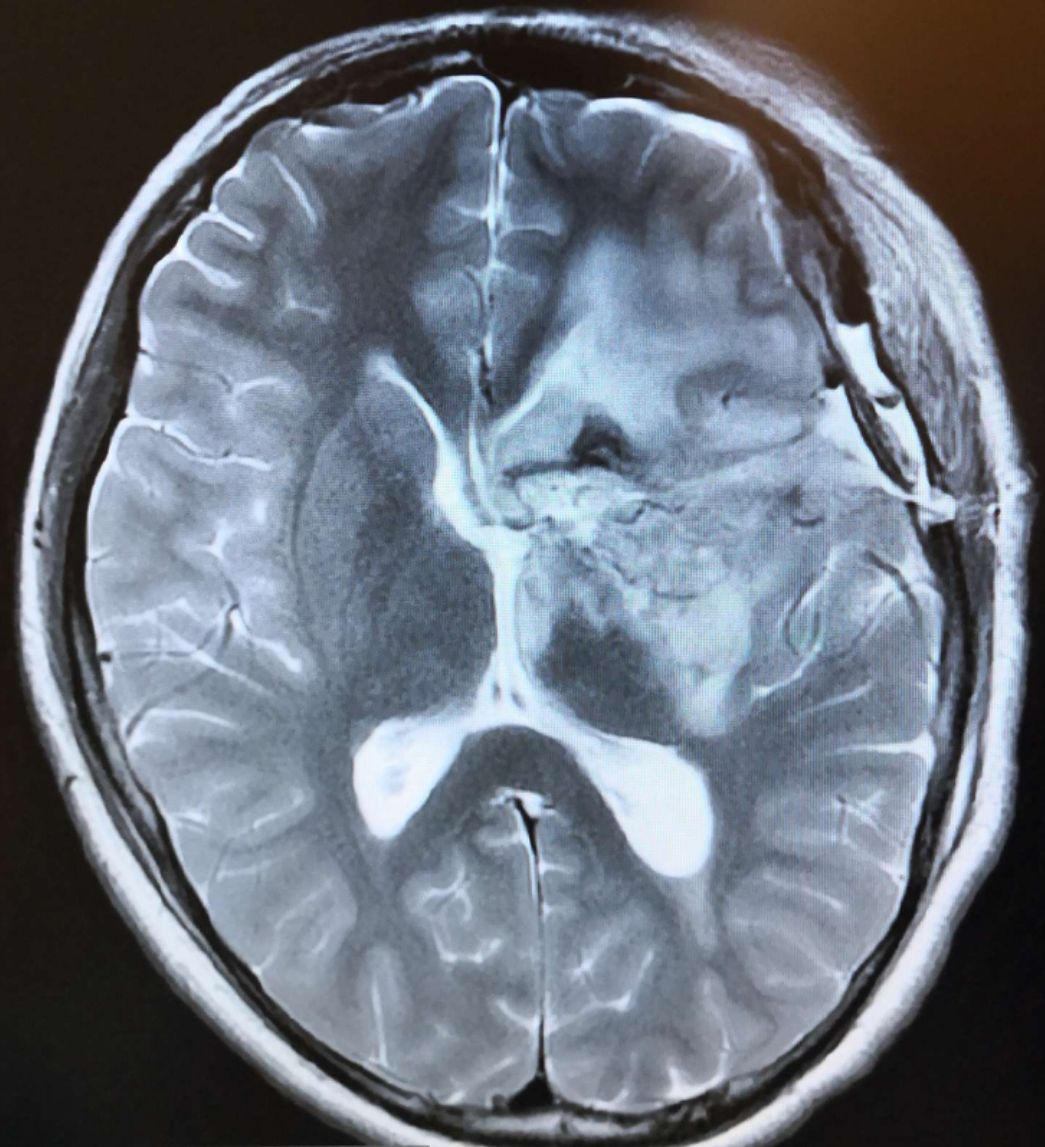

术前头颅MRI T2显示:左侧基底节巨大占位病灶(61*62mm),呈高、等、低混杂信号,脑室受压,中线移位明显。

术前头颅MRI DWI显示:左侧基底节巨大占位病灶(49*53mm),呈高、低信号,脑室受压,中线移位明显。